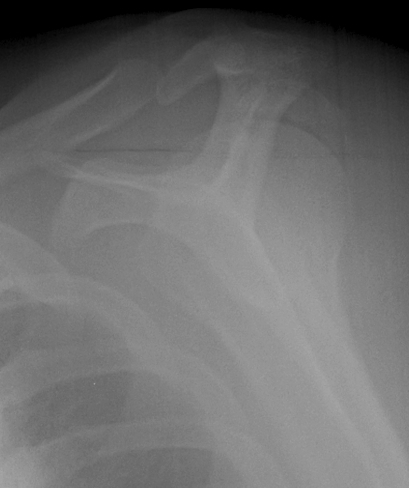

proximal humerus fracture Background ORIF with locking plate Arthroplasty Greater tuberosity fractures Lesser tuberosity fractures / avulsions Book traversal links for Proximal humerus fractures ‹ Pectoralis Major Tears Up Background ›